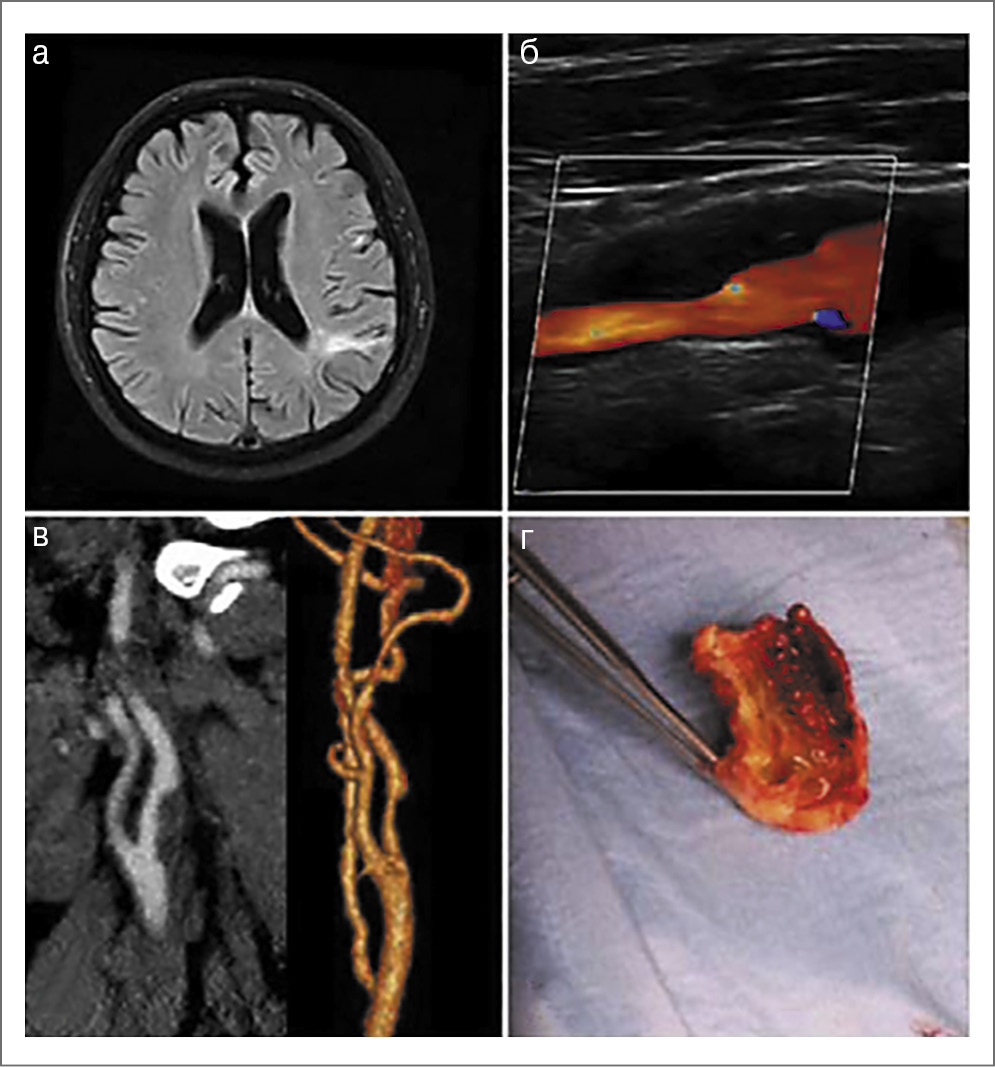

Инфекционный эндокардит. Каждый 5-й случай инфекционного эндокардита осложняется развитием инсульта, а еще у 40% больных наблюдаются бессимптомные церебральные инфаркты [15]. При этом в 1-й месяц риск развития мозговой катастрофы повышен в 20 раз [16]. Помимо ИИ острый инфекционный эндокардит может привести к развитию церебральных инфекционных аневризм, субарахноидального кровоизлияния, абсцессов и менингита/менингоэнцефалита (рис. 1, 2) [17].

Рис. 1. Клинический пример. Мужчина 35 лет перенес ИИ с поражением разных сосудистых бассейнов: а – инфаркт в бассейне левой и правой СМА; б – геморрагическая трансформация в зоне инфаркта в левой СМА (МРТ Hemo); в –инфекционный эндокардит АК на ЭхоКГ (красная стрелка указывает на вегетацию), в посевах крови – Staphylococcus epidermidis; г – резецированная клапанная вегетация (при протезировании АК).